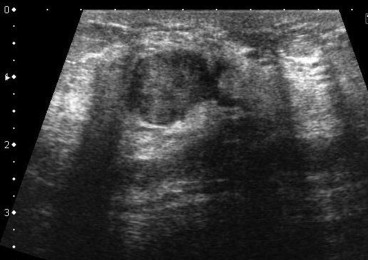

The cystic lesion and dilated mammary duct were fully removed, and could be seen ...

Figure 4.

The cystic lesion and dilated mammary duct were fully removed, and could be seen in the resected specimen.

The pathological diagnosis was intraductal papilloma of the breast.

Figure 5.